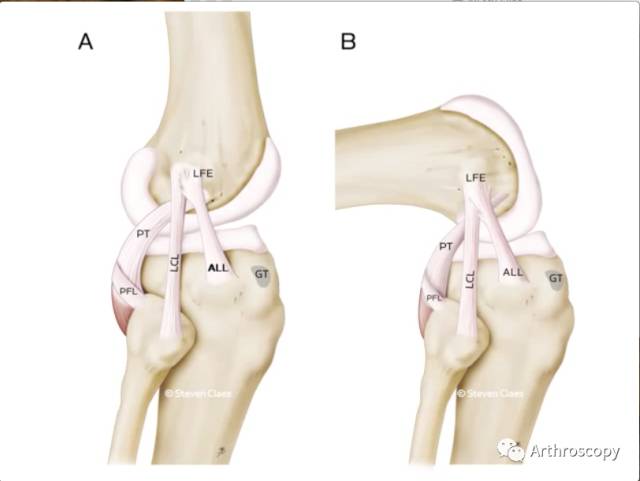

来自比利时鲁汶大学医院的Dr. Steven Claes在41例解剖中发现ALL的存在,并以"The Pivot Shift Unraveled: why we disagree with Dr.Freddie Fu"为题,公开叫板前交叉韧带业界大牛Freddie Fu。

但是,随着膝关节周围韧带结构的不断解剖完善,人们发现,膝关节外侧的前外侧韧带(Anterolateral Ligament ,ALL)在稳定膝关节旋转中有着重要的作用,它可以增加膝关节的旋转稳定性,防止过度内旋。因此,它的存在可能使得我们一直认为的轴移试验在鉴别前交叉韧带损伤中的特异性大打折扣。

综上,研究发现ALL位于股骨外侧髁外侧副韧带止点的前下方与胫骨Gerdy结节和腓骨头的中间,维持膝关节旋转稳定。

因此,Arth君认为:在Segond骨折的前交叉损伤及术后重建前交叉韧带后有旋转不稳时,应考虑重建前外侧韧带。

PFL:腘腓韧带;PT:腘肌腱;LCL:外侧副韧带;ALL:前外侧韧带;LFE:股骨外侧髁;GT:Gerdy结节